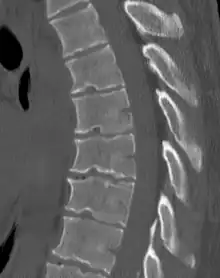

| Scheuermann's disease on lateral Xray of the T spine | |